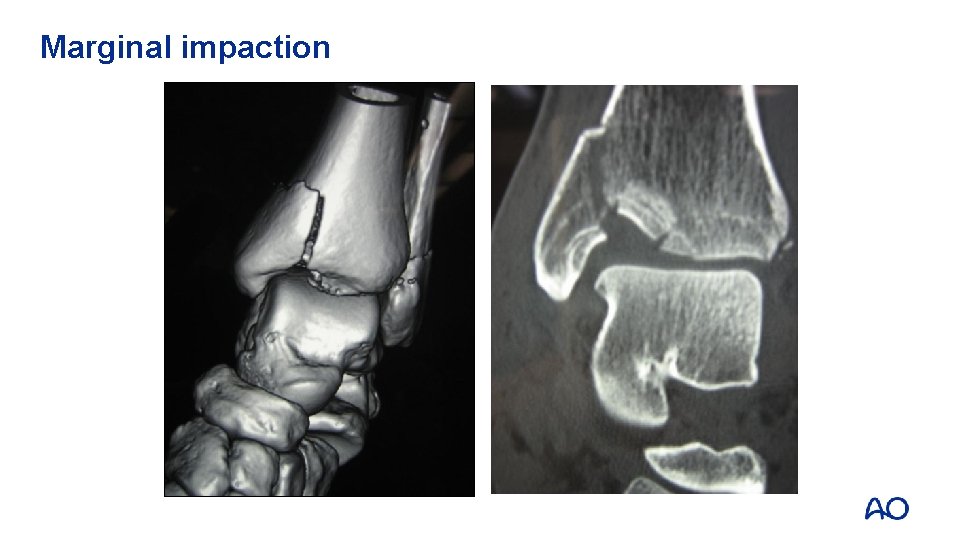

Marginal impaction